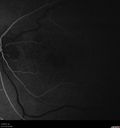

74 year old man caucasian man: The patient started having trouble with his vision after his stroke 10/9/17. He noticed after recovery that his peripheral vision had declined. He doesn't notice a difference between his two eyes. He has been having trouble focusing together his two eyes. After his stroke he was not able to read. He could trace letters but not see. He is having speech and occupational therapy at the moment. VA OD: sc20/125-2 PH20/125-2 NccJ1+ VA OS: sc20/63-2 PH20/100-2 NccJ1 Vision improved to 20/20 with Lucentis

Polypoidal Choroidal Vasculopathy Left Eye398 views74 year old man with vision loss to 20/100 over a few months. He improved to 20/20 with Lucentis. The color and ICG show the polyps.00000